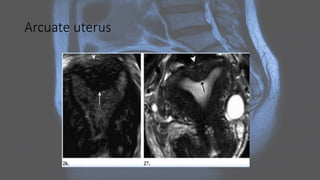

Arcuate uterus

Radiographic features Ultrasound: • shouldbe performed initially • confirms any structural abnormalities of the genital tract • sometimes cannot help to identify the type of MDA (especially on 2D imaging alone) • 3D coronal transvaginal imaging has a high degree of diagnostic accuracy and ideally should be performed in the secretory phase of the menstrual cycle

• 21.

MRI: • valuable non-invasivetechnique • evaluation of the female pelvic anatomy • accurate Müllerian duct anomaly classification